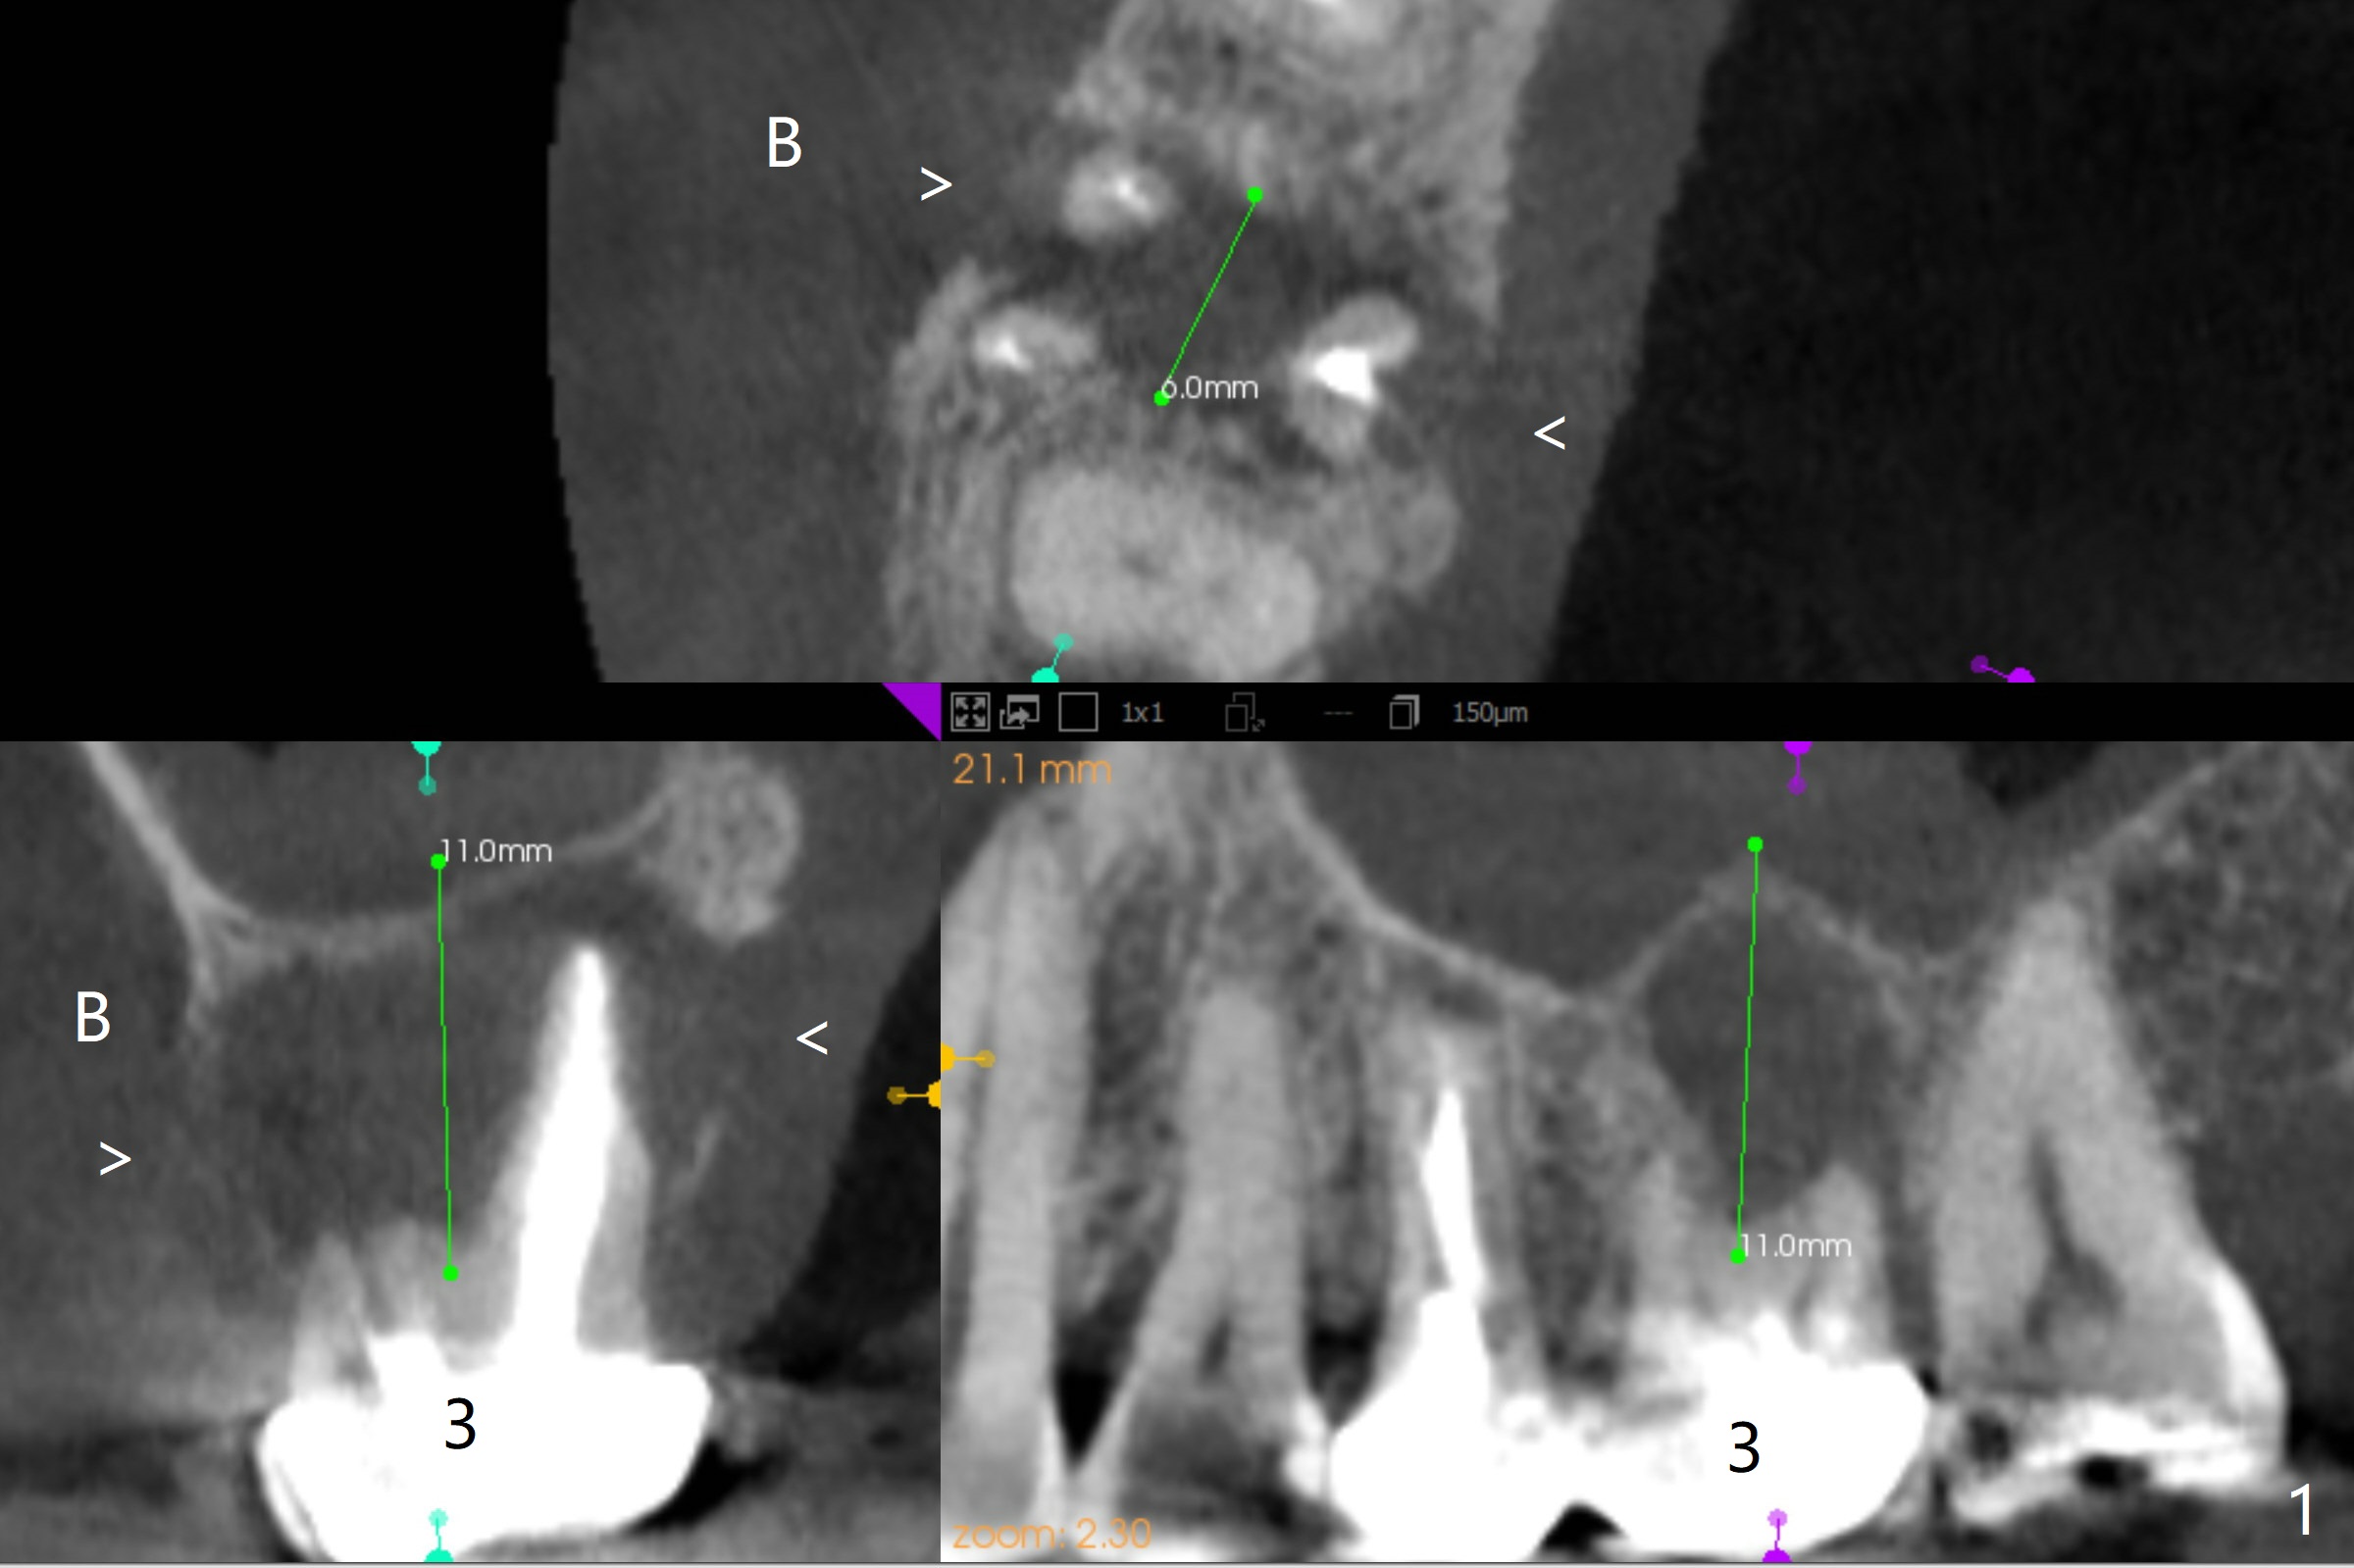

CT was taken prior to #30 crown fabrication and analyzed after crown cementation. It appears that the tooth #3 is non-salvageable (Fig.1). CMC (1,2) is indicated for #14 implant placement (Fig.2), while it seems necessary to place the 1st implant at #19 because of the cantilever FPD (Fig.4). Please note the submandibular fossa associated with implant placement at #19 and 31 (Fig.3,4 *).